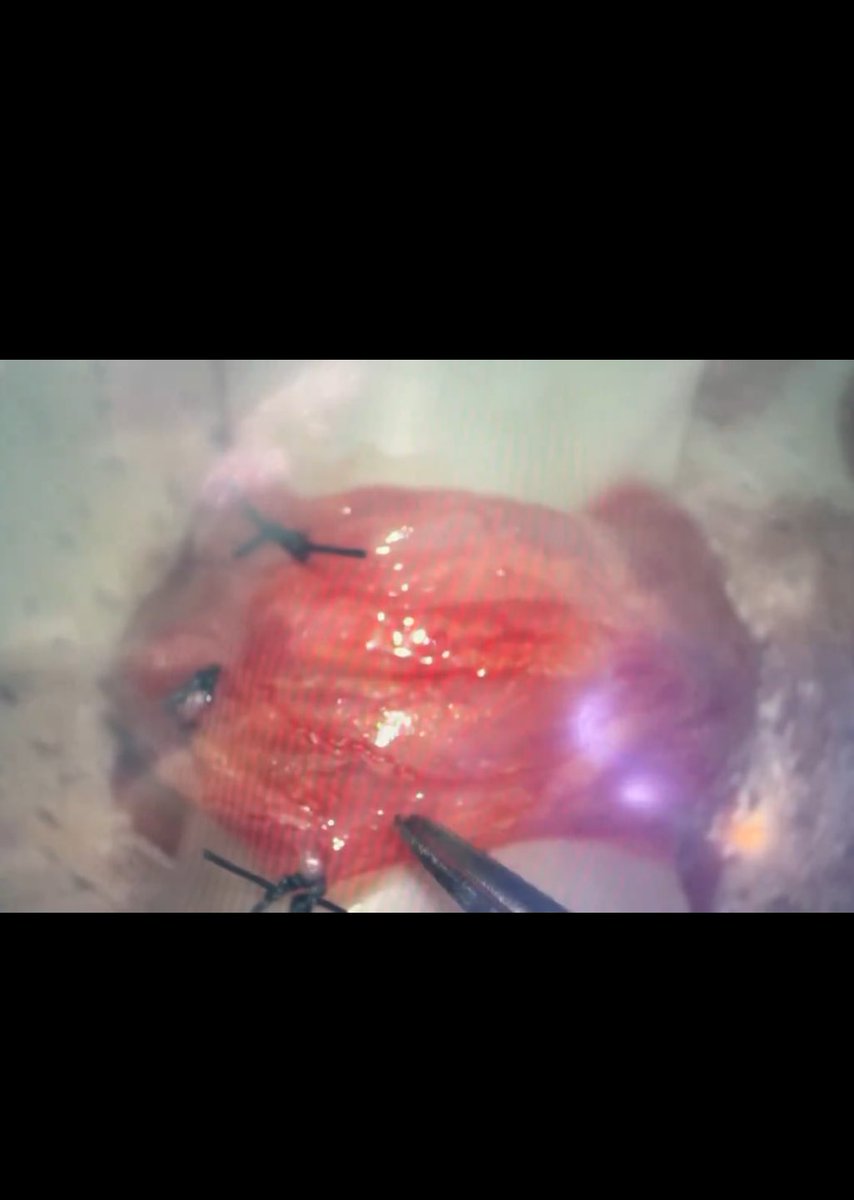

10- ماذا عن عدد الأوردة؟ وضحنا بالسابق ان اكثر الدراسات تتكلم عن ربط عدد بسيط من الأوردة (تقسّم غالباً لغرض الدراسات الى ربط أقل من ٥ أوردة. ، ٥ إلى ١٠ ، أكثر من ١٠ أوردة). ووضحنا بالسابق أنه يمكن من مجرد مشاهدتك للصور الجراحية المنشورة (هنا موضح ربط ٣ أوردة فقط!) أن تعرف ان عدد الأوردة المربوطة اقل بكثير من الذي نراه بشكل دائم بالقسطرة. يمكنك كذلك أن تشاهد مقاطع للجراحة باليوتيوب (لكن لا أنصح شخصياً بذلك) لترى كيف يتم تمزيق وكي الأغشية للوصول (لهذا العدد القليل) باستخدام الأداة الكاوية.

١٢- كذلك، هناك قنوات ليمفاوية اكبر من هذه الأوردة وربطها يسبب القيلة. غالباً يتم ربط الأوردة الكبيرة التي يمكن التعرف عليها. ترك أوردة دون ربط هو أحد أهم أسباب عودة الدوالي بسرعة او عدم اختفائها من الأساس. بالصورة نجد وريد داخلي لم يتم ربطه بجانب الكلبسات المعدنية من الجراحة.

١٤- لكن ، لماذا لا يتم جراحياً ربط الوريد الخصوي كذلك؟ لأن الوريد الخصوي يمتد لأعلى الظهر. ويخرج الى الخصية عن طريق القناة الاربية. تمزيق الأغشية بالمنطقة الأربية قد يؤدي الى حدوث مشكلة اكبر وهي الفتق. ماذا عن عملية منظار البطن؟ هذه احدى الطرق التي قام بعض جراحين المسالك من الغرب باستخدامها لربط الوريد الخصوي. لاحظ وجود الشعيرات الدموية بالأغشية (سهم).

١٦- عند اجراء العملية الغريبة التي ذكرناها (كانت تعمل للأسف بالسعودية وفشلت) فإن تمزيق الاغشية قد يؤدي الى القيلة بنسبة أعلى. كذلك ، لا يتم ربط دوالي الخصية اسفل القناة الاربية! لا زال الغرب من الجراحين يحاول استكشاف طرق جراحية جديدة (مثل استخدام الروبوت الجراحي بالدراسة المرفقة التي عملت في ايطاليا قبل سنتين) للحصول على نتائج ممثالة للقسطرة. كلها لم تنجح حتى الآن ، وكلها جراحات تعمل بتخدير كامل.

١٧- ماذا عن تجمع الحرارة والدم حول الخصية؟ هذه الدوالي تمتد الى حول الخصية والبربخ. الربط الجراحي يكون بمستوى واحد فقط فوق الخصية مع ترك كل هذه الاوردة المتضخمة المحتقنة بالدم حول الخصية. لذلك في غالبية الحالات يكون التحسن بالاعراض والحيوانات المنوية مؤقتاً. هذه حالة لدوالي تم ربطها جراحياً ، لاحظ انه بالاضافة الى عدم ربط كل الاوردة عند مكان الشق الجراحي(وريد داخلي كبير لم يربط بالأزرق ، أوردة خارجية خلفية لم تربط بالأصفر، شبكة دوالي كبيرة -سهم احمر- محتقنة حول الخصية لم يتم لمسها).